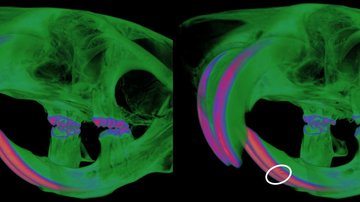

Cole JB, Manyama M, Kimwaga E, Mathayo J, Larson JR, Liberton DK, Lukowiak K, Ferrara TM, Riccardi SL, Li M, Mio W, Prochazkova M, Williams T, Li H, Jones KL, Klein OD, Santorico SA, Hallgrimsson B, Spritz RA: Genomewide Association Study of African Children Identifies Association of SCHIP1 and PDE8A with Facial Size and Shape. PLoS Genet 2016 12(8): e1006174.